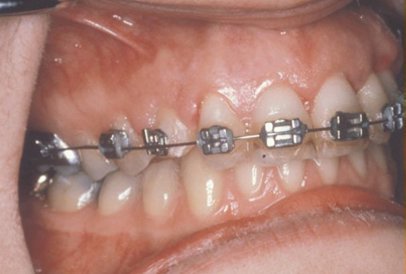

In cases where the eyeteeth will not erupt spontaneously, the orthodontist and oral surgeon work together to get these unerupted eyeteeth to erupt. Each case must be evaluated on an individual basis but treatment will usually involve a combined effort between the orthodontist and the oral surgeon. The most common scenario will call for the orthodontist to place braces on the teeth (at least the upper arch). A space will be opened to provide room for the impacted tooth to be moved into its proper position in the dental arch. If the baby eyetooth has not fallen out already, it is usually left in place until the space for the adult eyetooth is ready. Once the space is ready, the orthodontist will refer the patient to the oral surgeon to have the impacted eyetooth exposed and bracketed.